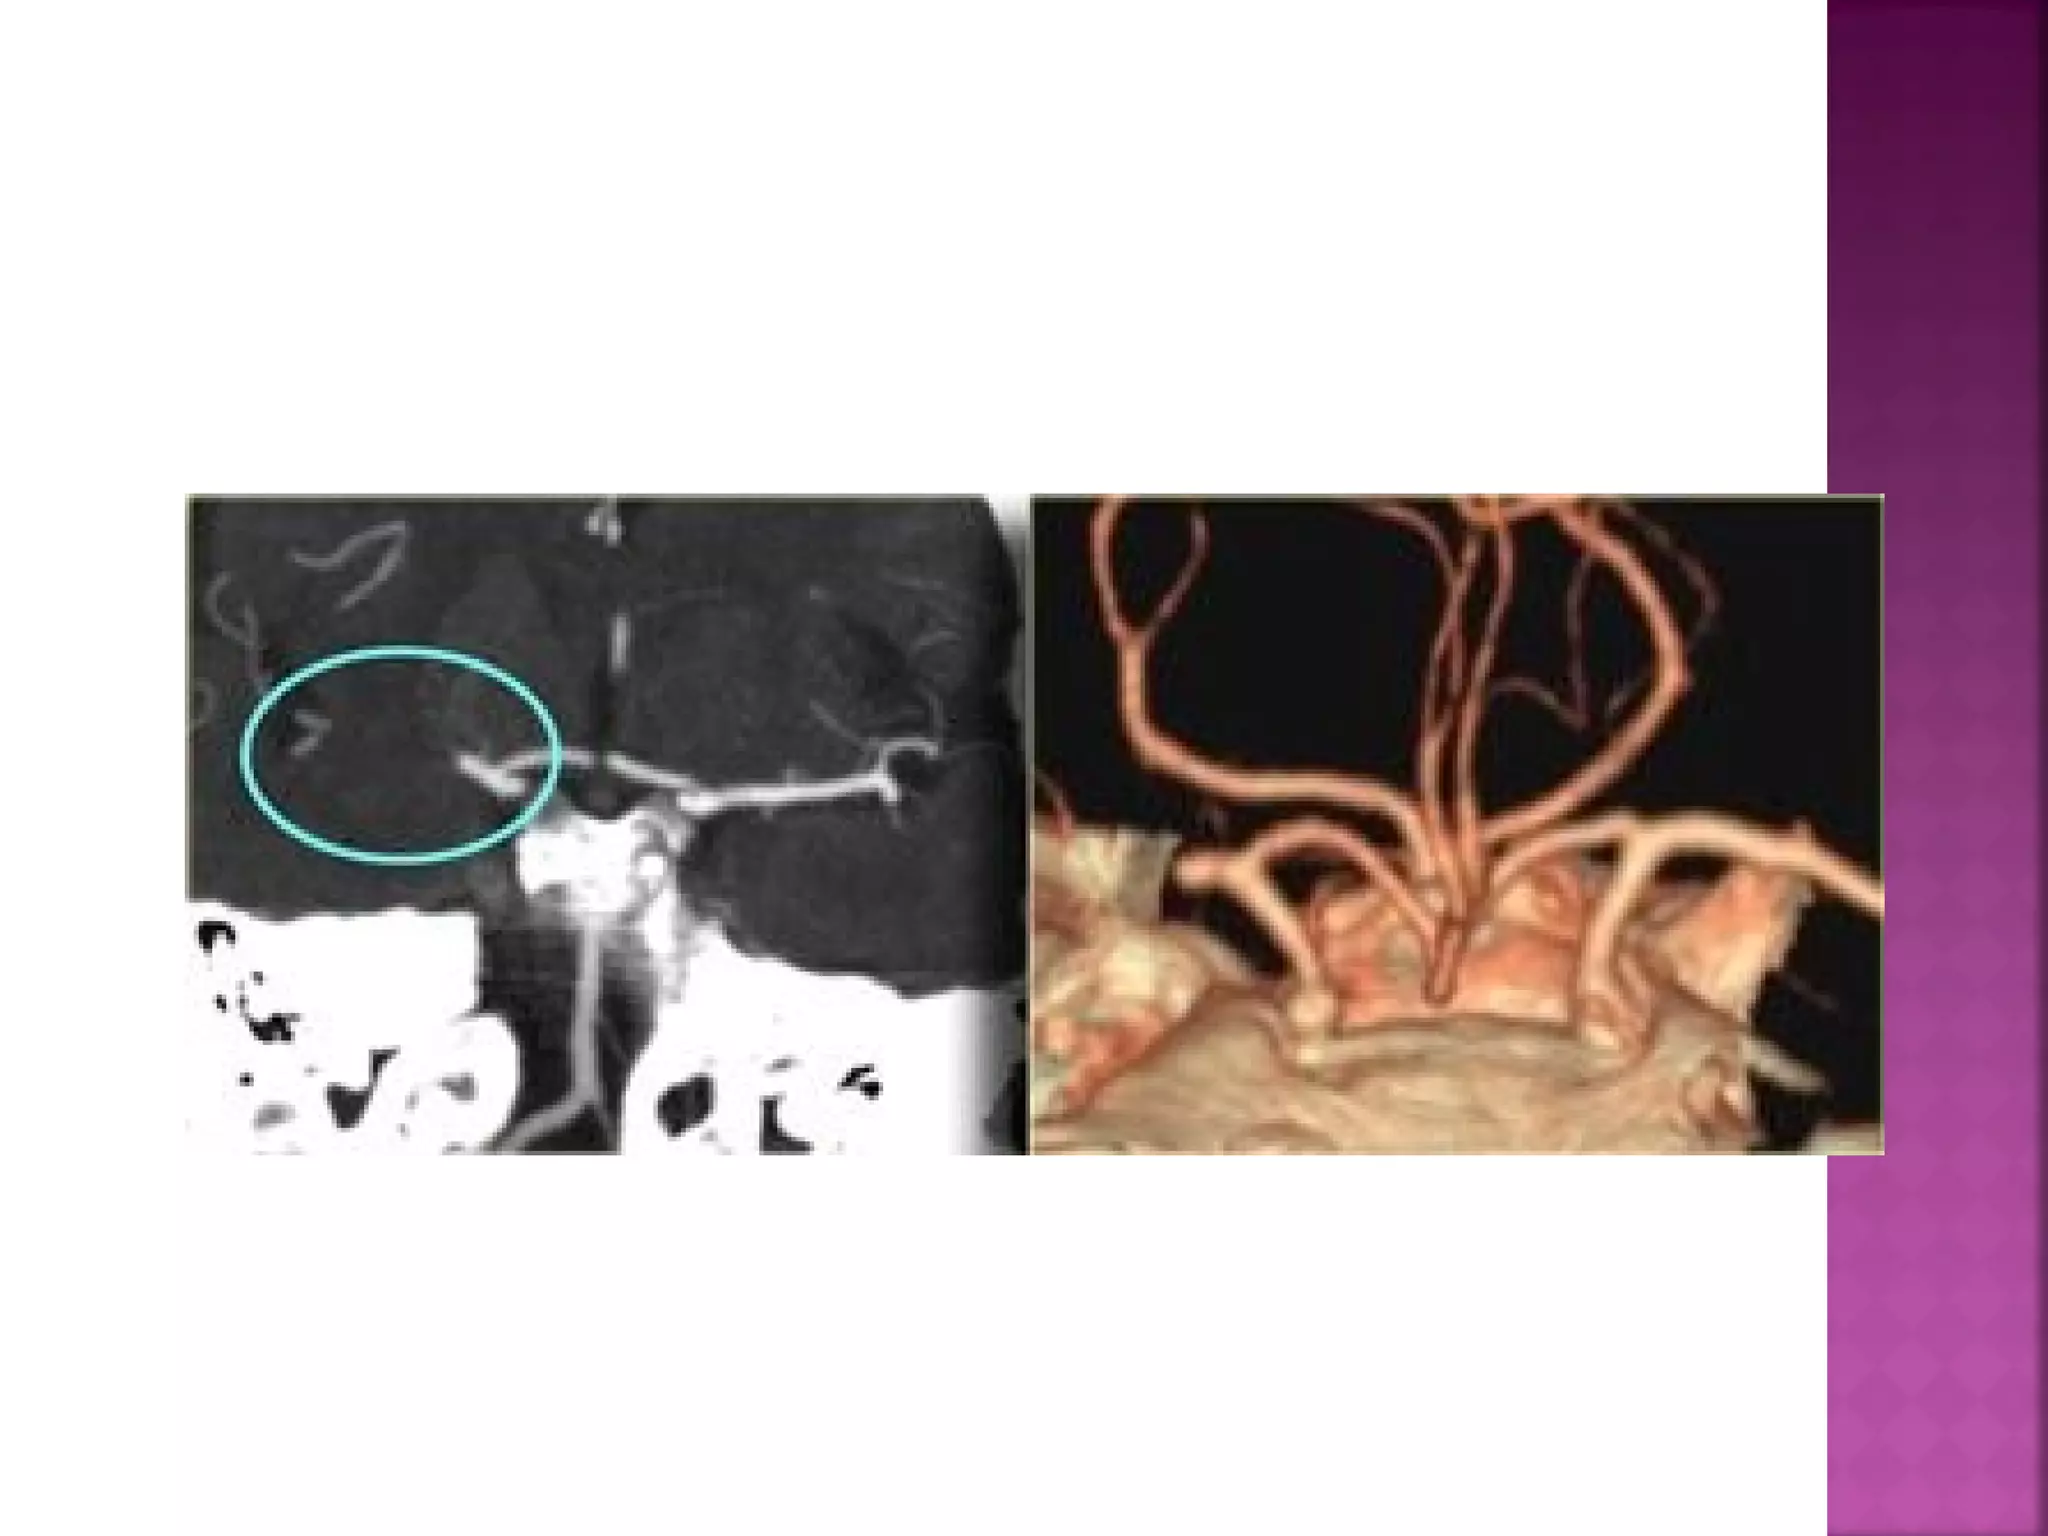

The goal ofimaging in a patient with acute stroke is:  Exclude hemorrhage  Differentiate between irreversibly affected brain tissue and reversibly impaired tissue (dead tissue versus tissue at risk)  Identify stenosis or occlusion of major extraand intracranial arteries

 This is aresult of thrombus or embolus in the MCA.